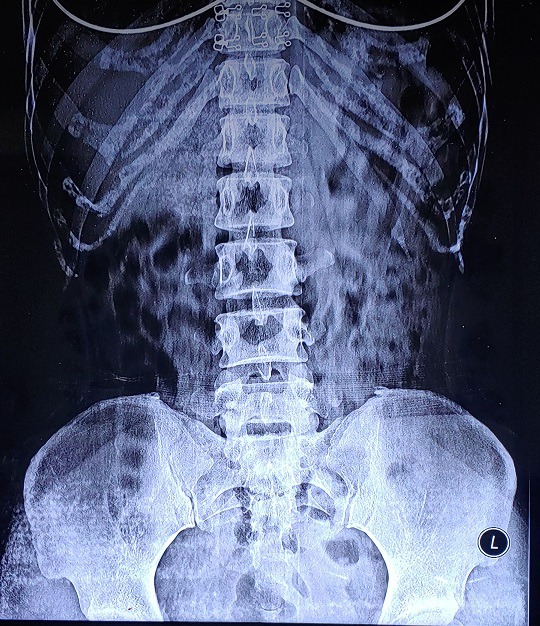

2017.12.30 경추 회전변위/ 요추 회전변위 / 디스크돌출/ 2020.1.10 역C자 목

당시에는 제가 몇 번 디스크라고 말도 안 해주셔서 몰랐는데 이번 지도사 과정을 배우면서 스스로 알게됐네요. 4-5번 디스크 돌출과 약간 요추후만..으로 보이네요.

그리고 엉덩이는… 네, 소멸한 상태구요.